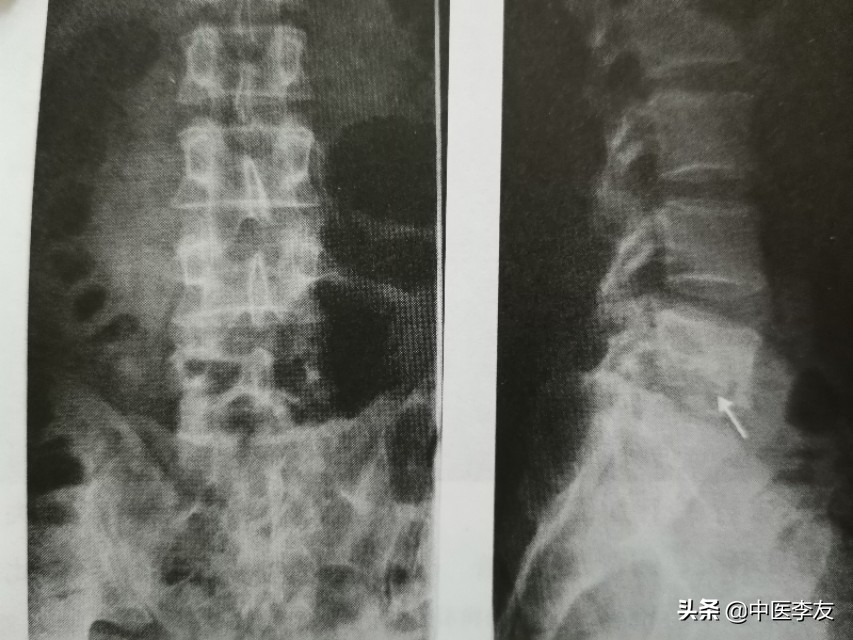

1.X线:①骨质破坏:表现为低密度骨质缺损区,边缘无硬化。

②椎间隙变窄或消失,因椎间盘及软骨终板被破坏,椎间盘破坏严重者可导致相邻的椎体融合在一起,为诊断脊椎结核的重要依据。

③后突畸形:为脊椎结核较特征性表现之一,为多个椎体明显破坏所致。

④冷性脓肿:腰椎结核可形成腰大肌脓肿,表现为腰大肌呈弧形向外突出高密度影,胸椎结核形成椎旁脓肿,表现为胸椎两旁梭形软组织肿胀高密度影,颈椎结核形成咽后壁脓肿,表现为咽后壁软组织影增宽,并呈弧形前突,较长时间的冷性脓肿可有不规则钙化。

⑤死骨:较少见,有时见于脊椎中心型结核,表现为砂粒状死骨。